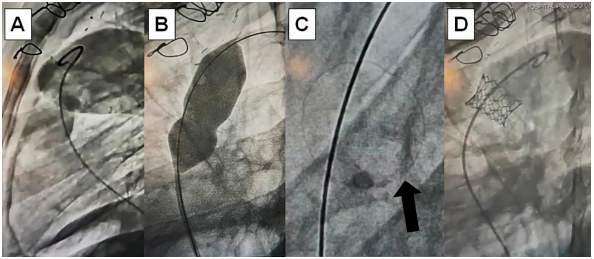

Fig. 1.

(A) Angiography of Epic Supra™ (St Jude Medical, USA) dysfunctional bioprosthesis in pulmonary position in strict 90 °left lateral oblique projection. (B) Ultrahigh pressure non-compliant balloon to produce intentional valve ring fracture. (C) Fractured valve ring (arrow). . (D) Angiography in the same initial projection: Myval™ balloon-expandable valve (Meril, India) implanted with “valve-in-valve” technique in pulmonary position.